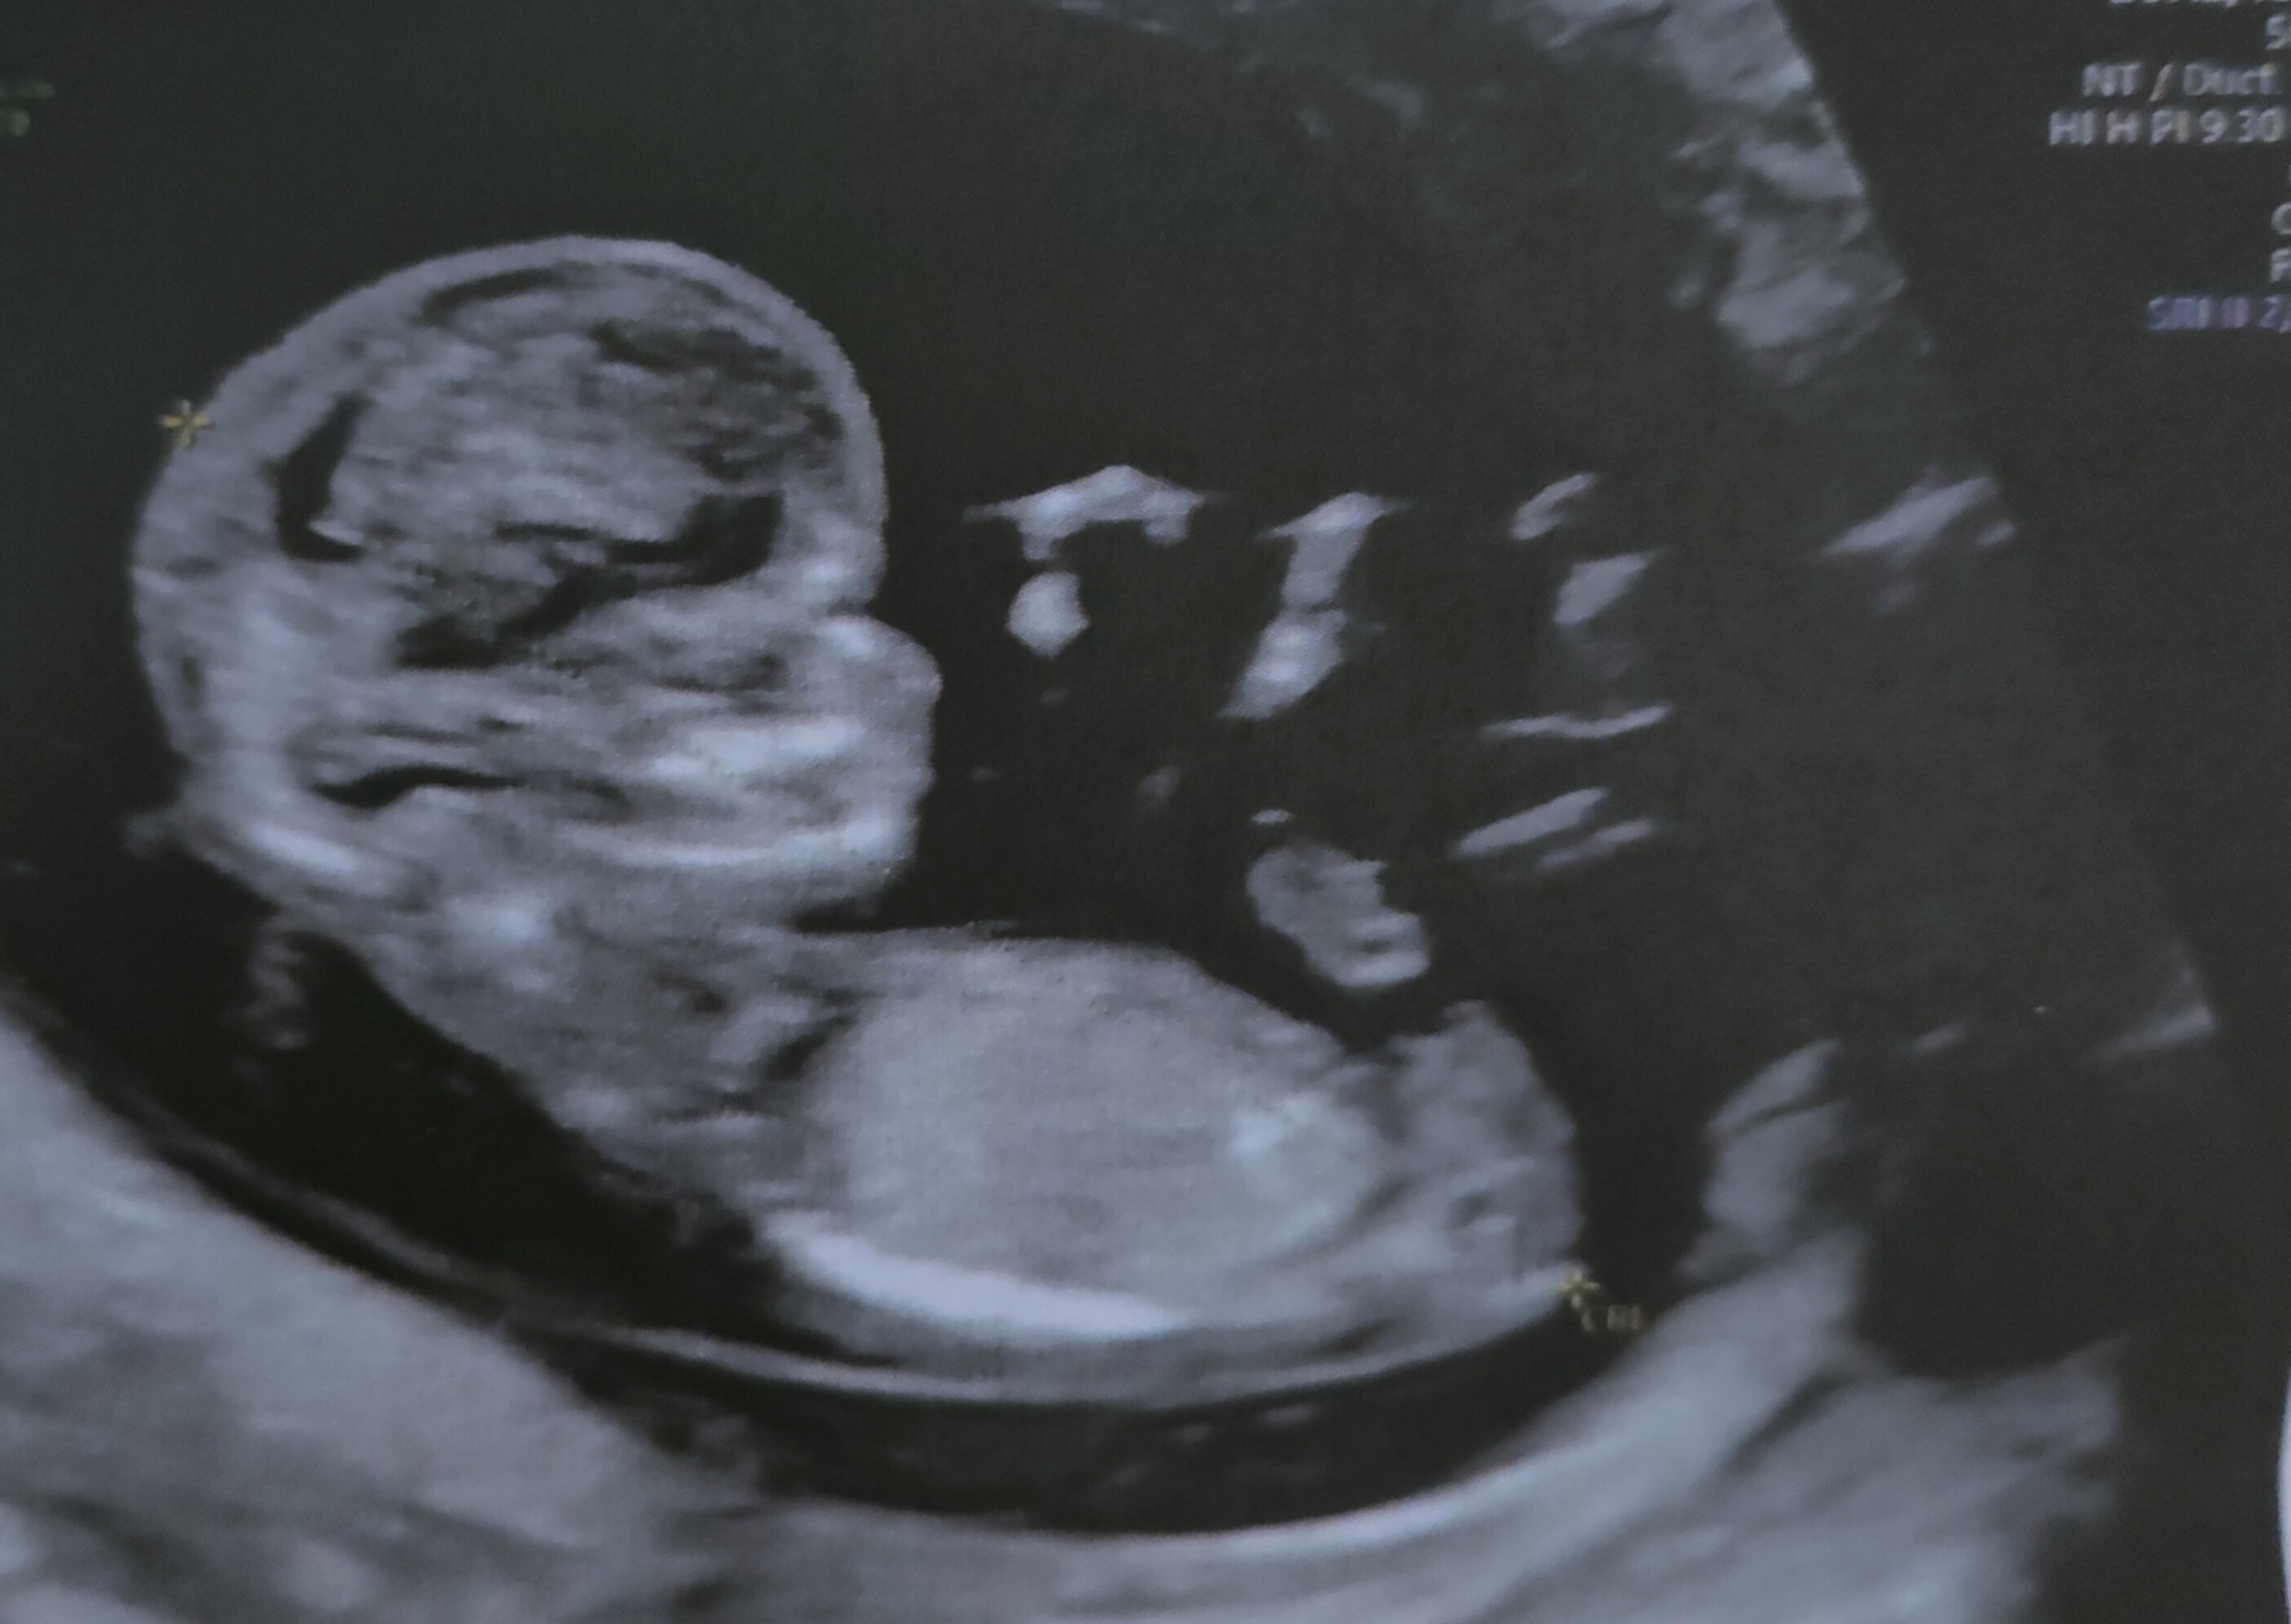

Gratuluję wszystkim wizyt, dużo dzisiaj produkujecie, ja dalej w emocjach więc nie dam rady nadrobić ale wrzucam zdjęcie malucha z dzisiaj. Dalej w szoku że dziewczynka 🙆

Załączniki

• IMG_20230104_185237.jpg

IMG_20230104_185237.jpg

451,7 KB · Wyświetleń: 104